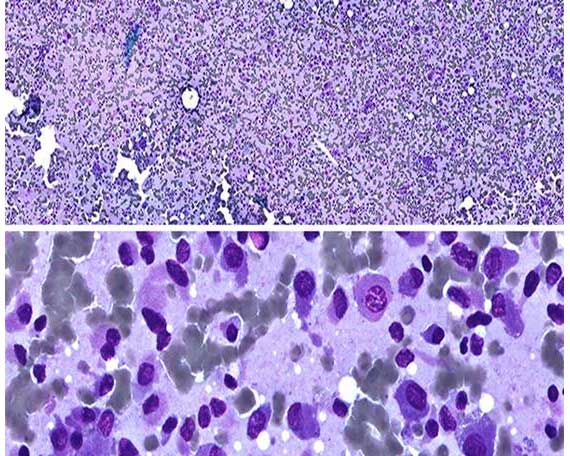

Immersion scanning with high magnification and high definition

Sample scanning with high magnification (60x, 100x), when the high quality of images is required. For example, for blood and bone marrow samples.

Optional Special high definition objectives are used for immersion scanning. These objectives work with immersion oil.